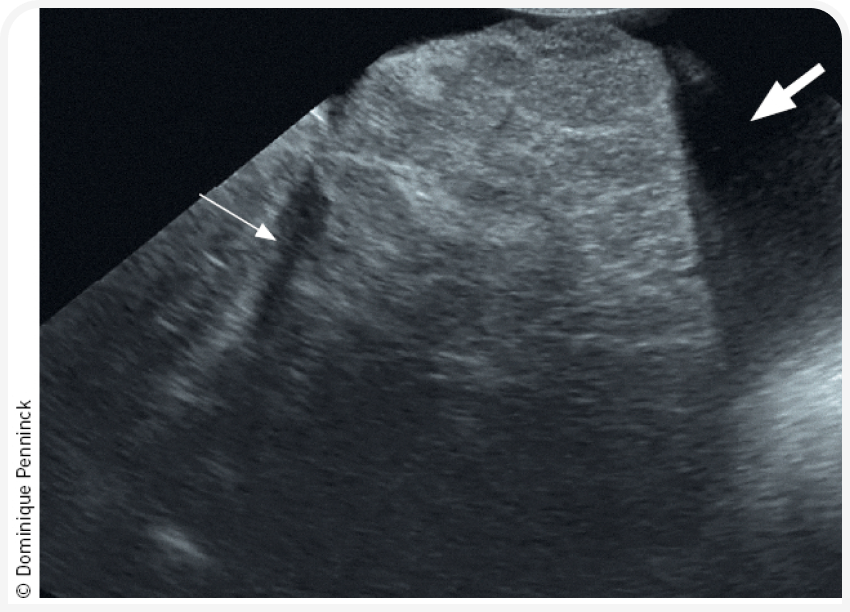

На поздних стадиях ХГ печень при ультразвуковом исследовании может быть маленькой, с неровными краями (Рисунок 3) и признаками портальной гипертензии, к которым относят асцит, отечность (особенно заметную в области желчного пузыря и поджелудочной железы), снижение скорости портального кровотока (средняя скорость меньше 10 см/с по сравнению с нормальным диапазоном 10,5-25,7 см/с) или гепатофугальное направление кровотока, а также наличие множественных приобретенных портосистемных шунтов, обычно в виде сложного сплетения небольших извилистых сосудов каудальнее левой почки (20).